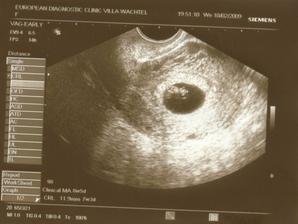

29.1.2009 kontrola u doktora - malilinkatý gestační váček